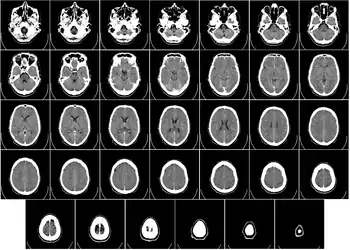

Компьютерная томография головы

Компьютерная томография (КТ) или компьютерная аксиальная томография (КАТ) использует серии рентгеновских лучей, направленных на голову, с большого количества разных направлений. Обычно её используют для быстрой визуализации ЧМТ. При КТ используют компьютерную программу, что осуществляет цифровые интегральные вычисления (инверсию преобразования Радона) измеряемой серии рентгеновских лучей. Она вычисляет, насколько эти лучи абсорбируются объёмом головного мозга. Обычно информация представлена в виде срезов мозга[4].